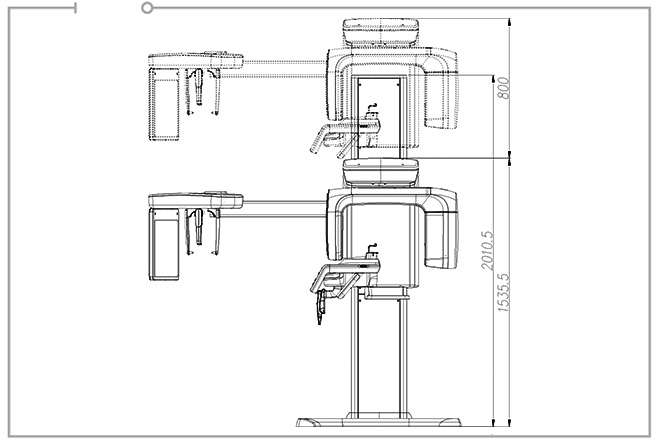

| 功能 | CBCT, 全景,头颅侧位 | |

| 焦点 | 0.5mm | |

| 体素 | 0.08mm~0.3mm | |

| 扫描时间 | CBCT | 4.9sec/9sec |

| 全景 | 7sec/13.5sec | |

| 标准头颅侧位 | 1.9sec | |

| 全头颅侧位 | 5.4sec | |

| 灰阶 | 14bit | |

| 管电压/管电流 | 60~99kvp/4~16mA | |